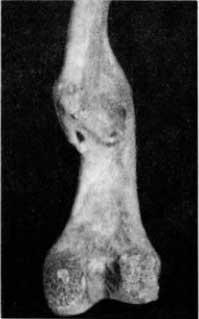

Большеберцовые кости подростка из погребения в Саркеле (X–XII вв.) характеризуются стадией окостенения, когда нет не только синостоза эпифиза с метафизом, но не видно бугристости большеберцовой кости, окостенения места прикрепления связки надколенника (рис. 29, А и Б; слева — патологически измененная кость, справа — здоровая).

Рис. 29. А — подострый остеомиелит левой большеберцовой кости подростка, отслойка и деструкция периоста, мелкие свищевые отверстия (вид спереди): Б — то же на боковой поверхности, рядом здоровая большеберцовая кость; В — деструкция значительного участка левой большеберцовой кости без четкого отграничения, отслойка периоста, полости и секвестры на рентгенограмме не видны.

На мацерированной большеберцовой кости (слева) видна деструкция в области проксимального метафиза и верхней трети диафиза. Поверхностный слой кортикального вещества на довольно значительном протяжении разрушен. Видны небольших размеров свищевые ходы (рис. 29, Б), а местами — частично окостеневшие неровные периостальные наслоения.

На рентгенограмме обнаруживается наличие довольно обширной деструкции губчатого вещества без четкого отграничения. Имеется неровность (изъеденность) кортикального слоя.

Слабо выражены периостальные наслоения (рис. 29, В). Не видно полостей и кортикальных секвестров. Изменения на почве гематогенного остеомиелита в подострой фазе.